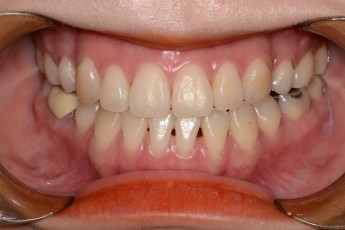

Before

After